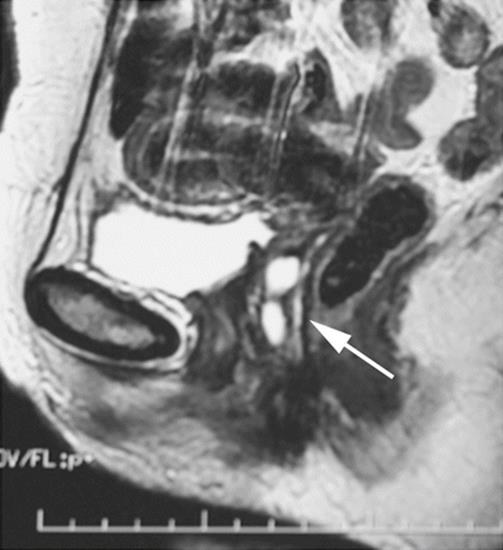

Fig. 8.1

Sagittal midpelvis MRI of a patient suffering from right labial pain and swelling, with pain during intercourse. A cystic lesion is seen in the distal vagina (arrow)